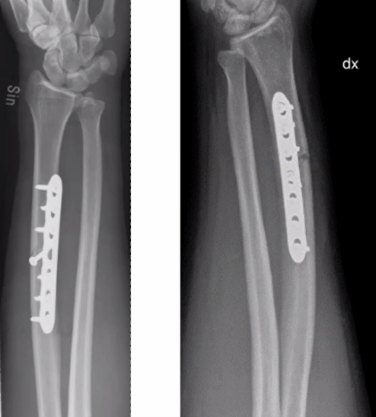

Q

65-årig kvinna

• Rökare, möjlig alkoholöverkonsumtion

• Tidigare kons beh distal radiusfraktur

• Ramlat över mattkant

• Sluten skada. NV intakt

Vad göra?

A

Plattan bra för att styra rotationskrafter, men direkt benläkning i radius och callusläkning i ulna